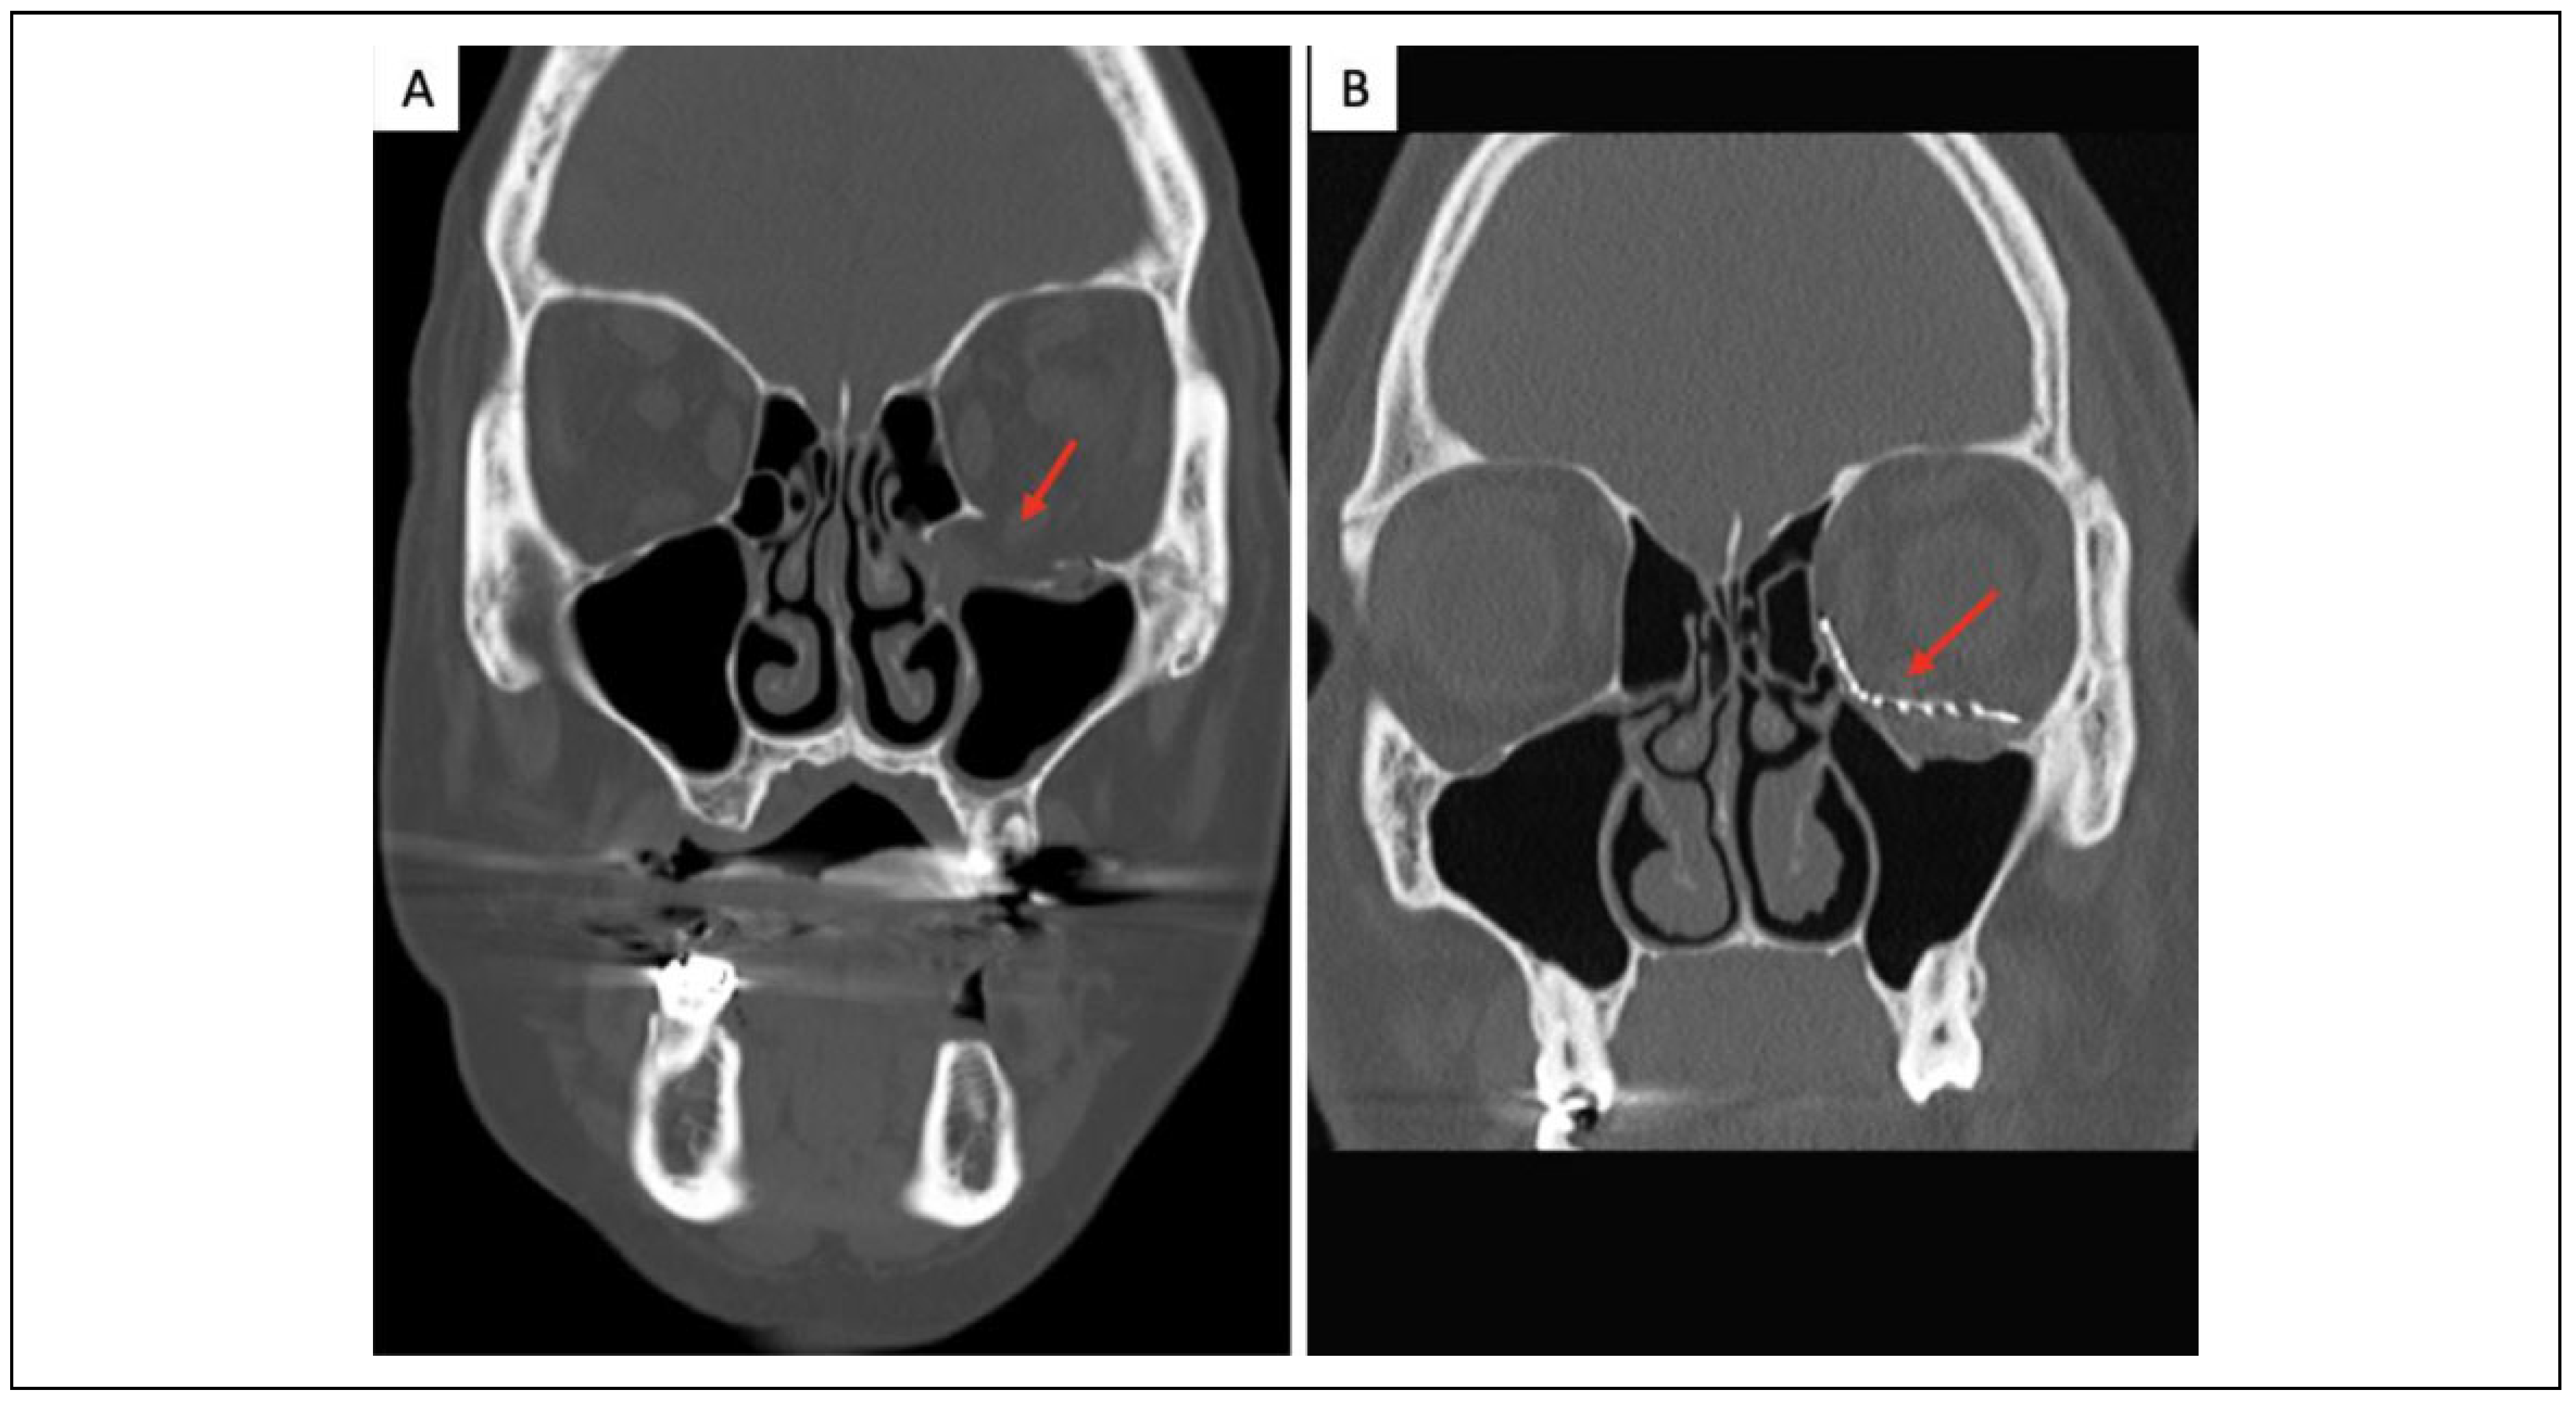

Indications and Timing of Repair

Delayed Repair